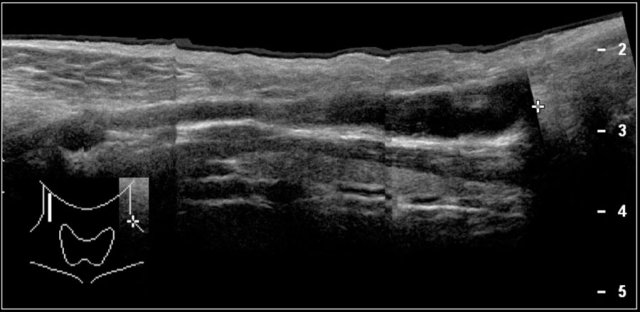

Thymus

The thymus is located in the upper mediastinum and can be visualized with a suprasternal scan plane.

With increasing age its echogenicity increases and becomes more granular.

Ultrasound is ideal to demonstrate the thymus as a cause of a widened upper mediastinum in infants.

Sometimes the thymus causes a swelling in the suprasternal notch on straining.

Such a herniating thymus can be demostrated with ultrasound.

Ultrasound image of the thymus in an eight-year-old boy.

Here a video of a six-month-old boy with a mass which was sometimes visible in the suprasternal notch.

While crying the thymus was seen to herniate in front of the trachea.